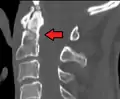

A fracture of the base of the dens as seen on plain X-ray

A fracture of the base of the dens as seen on CT